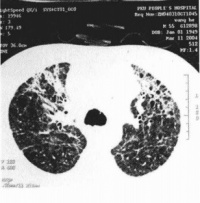

胸部X线检查早期可无异常,一般1周内逐渐出现肺纹理粗乱的间质性改变、斑片状或片状渗出影,典型的改变为磨玻璃影及肺实变影。可在2-3天内波及一侧肺野或两肺,约半数波及双肺。病灶多在中下叶并呈外周分布。少数出现气胸和纵隔气肿。CT还可见小叶内间隔和小叶间隔增厚(碎石路样改变)、细支气管扩张和少量胸腔积液。病变后期部分患者肺部有纤维化改变。